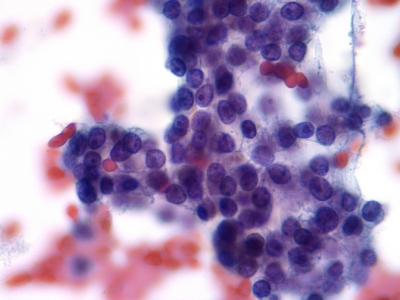

胚胎培养技术是指在受精卵, 在体外条件下进行体外培养, 使其具有发育到2细胞胚胎乃至囊胚, 并具发育成一个孤立个体的潜能。传统的胚胎移植一般选择卵裂期胚胎但其多胎...

囊胚培养是精子与卵子结合为受精卵后继续在培养箱内培养5至6天,然后再进行移植或冷冻的方法。囊胚培养有哪些优点呢?能够筛选掉发育潜力差的胚胎早期的胚胎(受精后第二或...

有一些姑娘的备孕之路卡在了最后胚胎这一关:明明验到两道杠了,却越来越淡最终生化流产。或是还没测到胎心,胚胎就停止了发育。后来不得已去做二代试管,明明有了等级不错的...

胚胎植入前基因诊断(PGD)正越来越多地用于试管婴儿,并显著提高试管婴儿成功怀孕的几率,尤其是此前那些原因不明的试管婴儿失败。据统计,一半以上的试管婴儿失败其实并...